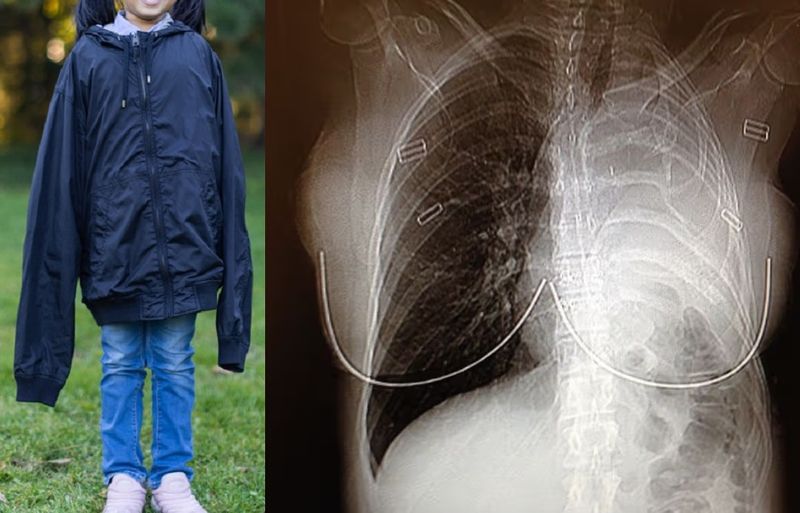

어릴 때 아빠 작업복 입고 놀던 여성이 20년 뒤 악성 폐암 진단을 받았대. 알고 보니 그 외투에 석면이 묻어 있었던 거지. 진짜 상상도 못할 일이다 ㄷㄷ 대부분 진단받고 1~2년 안에 세상을 떠난다고 하니 더 충격적이야.

석면은 건설 현장에서 많이 쓰이던 물질인데, 이걸 들이마시면 폐암을 유발할 수 있어. 이 여성도 어릴 때부터 꾸준히 석면에 노출됐던 거지. 처음엔 산후조리 피로인 줄 알았는데, 알고 보니 암이었다니… 결국 왼쪽 폐를 제거하는 큰 수술을 받았지만, 지금은 건강하게 지낸다고 해.